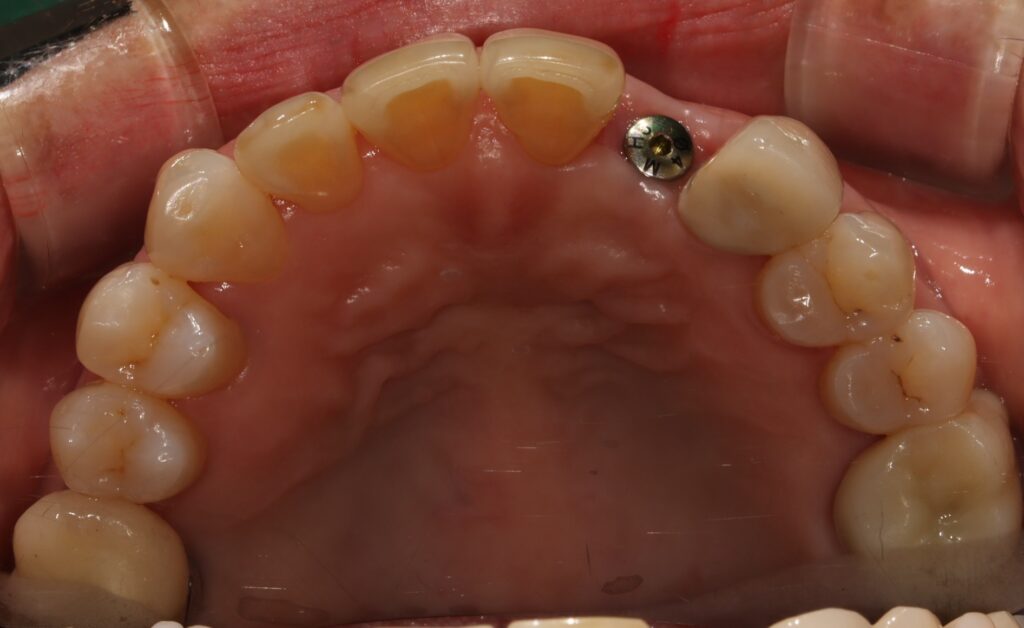

아래 앞니는 잇몸쪽으로 보이는

블랙트라이앵글과 잇몸 퇴축이 심하고

치아의 뿌리 형태를 다 채울 수는 없어서

뿌리쪽보다는 머리 부분의 공간만 채우는

디자인으로 해서 잇몸에 자극되지 않도록

치료를 마무리 하였습니다.